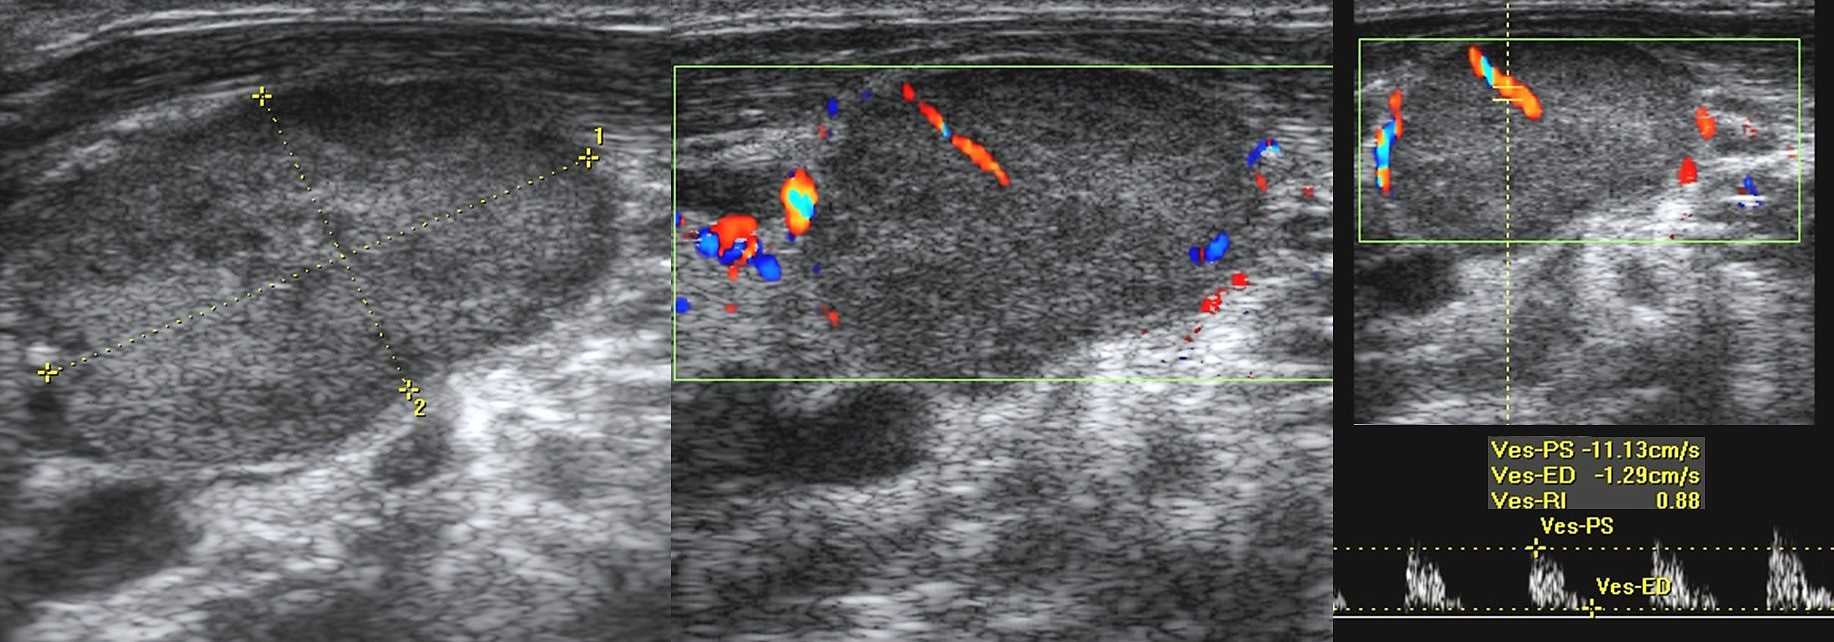

10 признаков злокачественного лимфоузла на УЗИ

- Кровоток дефективный — сосуды смещены, хаотично организованы, диаметр не уменьшается по направлению к капсуле, выраженный подкапсульный кровоток, аваскулярные зоны и др;

- Высокий индекс резистентности (RI >0,8) и пульсации (PI >1,5).

Рисунок. На УЗИ лимфоаденопатия с эхо-признаками злокачественного процесса: увеличенный (28х16 мм) лимфоузел, округлой формы (Д/К <2), гипоэхогенный без центрального рубчика; определяется подкапсульный кровоток, диаметр сосудов не уменьшается по направлению к капсуле, RI 0,88.